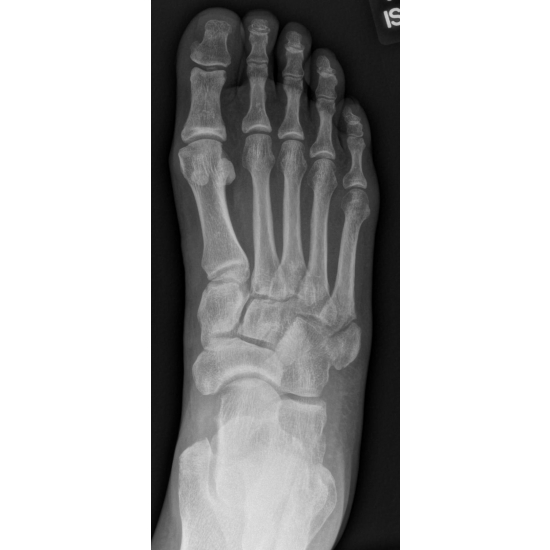

A 48-year-old-female runner complained of right lateral foot pain after running the bases at a softball game. She inverted her ankle on second base and felt a crack, but kept playing afterwards. She initially self-treated with a walking boot, but later went to the sports medicine clinic and was diagnosed with a right fifth metatarsal fracture. Case Photo #1 Case Photo #2